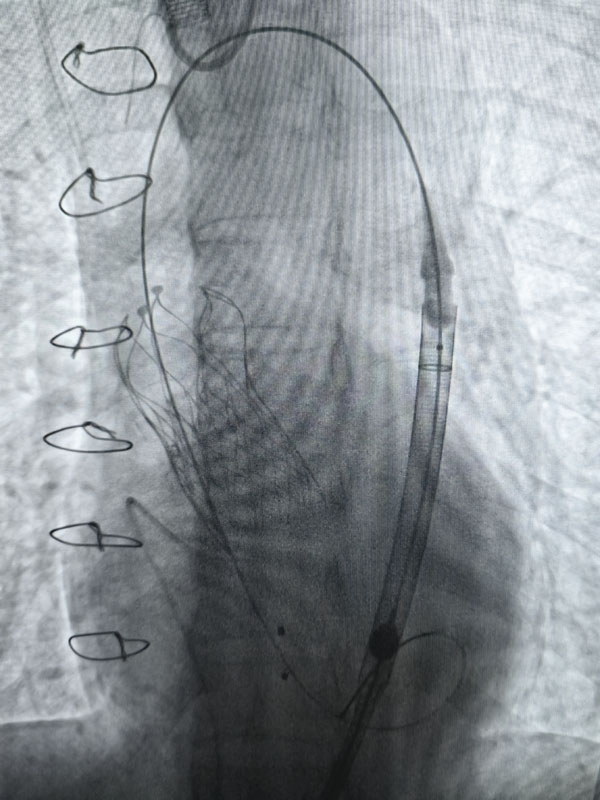

經過充分的術前準備,兩臺手術由心血管外科趙永波副主任主刀,趙偉超主治醫師、侯五輝主治醫師密切配合,選擇經皮股動脈穿刺,預埋縫合器,術中反復造影,準確定位釋放瓣膜,術后造影及超聲提示人工瓣膜開啟功能良好。為確保術中安全,體外循環小組全程保駕護航。患者生命體征平穩,術后一日均轉出監護室。